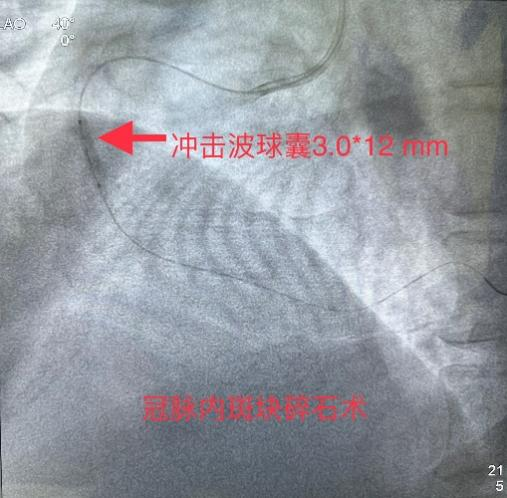

3月8日经过充分的术前准备,雷新军教授带领景林德博士和蔡安琪医生按照预定方案为患者实施了手术。冠脉造影示:RCA 2段慢性闭塞合并重度钙化,闭塞段长约30 mm,同向桥侧支供血使其远段显影(图3a);前降支散在斑块伴钙化,狭窄约25%-50%,并通过间隔支侧支循环向右冠逆向供血(图3b);回旋支11段狭窄约75%(图3c)。决定干预右冠:指引导管到位后在Guidezilla的支撑下,经Corsair微导管仔细操控GAIA 3rd穿过闭塞段进入远端血管真腔(图3d,e);然后通过微导管交换成旋磨导丝,使用1.5 mm Burr进行冠脉内斑块旋磨并抛光(图3f),造影见右冠恢复TIMI 3级前向血流,但2段残余狭窄最重处仍达90%(图3g);遂经导丝送入3.0*12 mm“Shockwave”冲击波球囊分段进行血管内碎石术:首先将压力充盈至4 atm后开始释放脉冲,松解钙化斑块,然后再将充盈压升至6 atm维持10秒,对靶病变进行低压球囊扩张成形(图3h);再次造影见右冠2段局限性夹层,闭塞段残余狭窄<10%(图3i),效果非常满意,遂由远及近衔接植入BioFreedom支架(图3j),历时约1小时手术成功,病人安返病房。

图3 经皮冠脉介入治疗